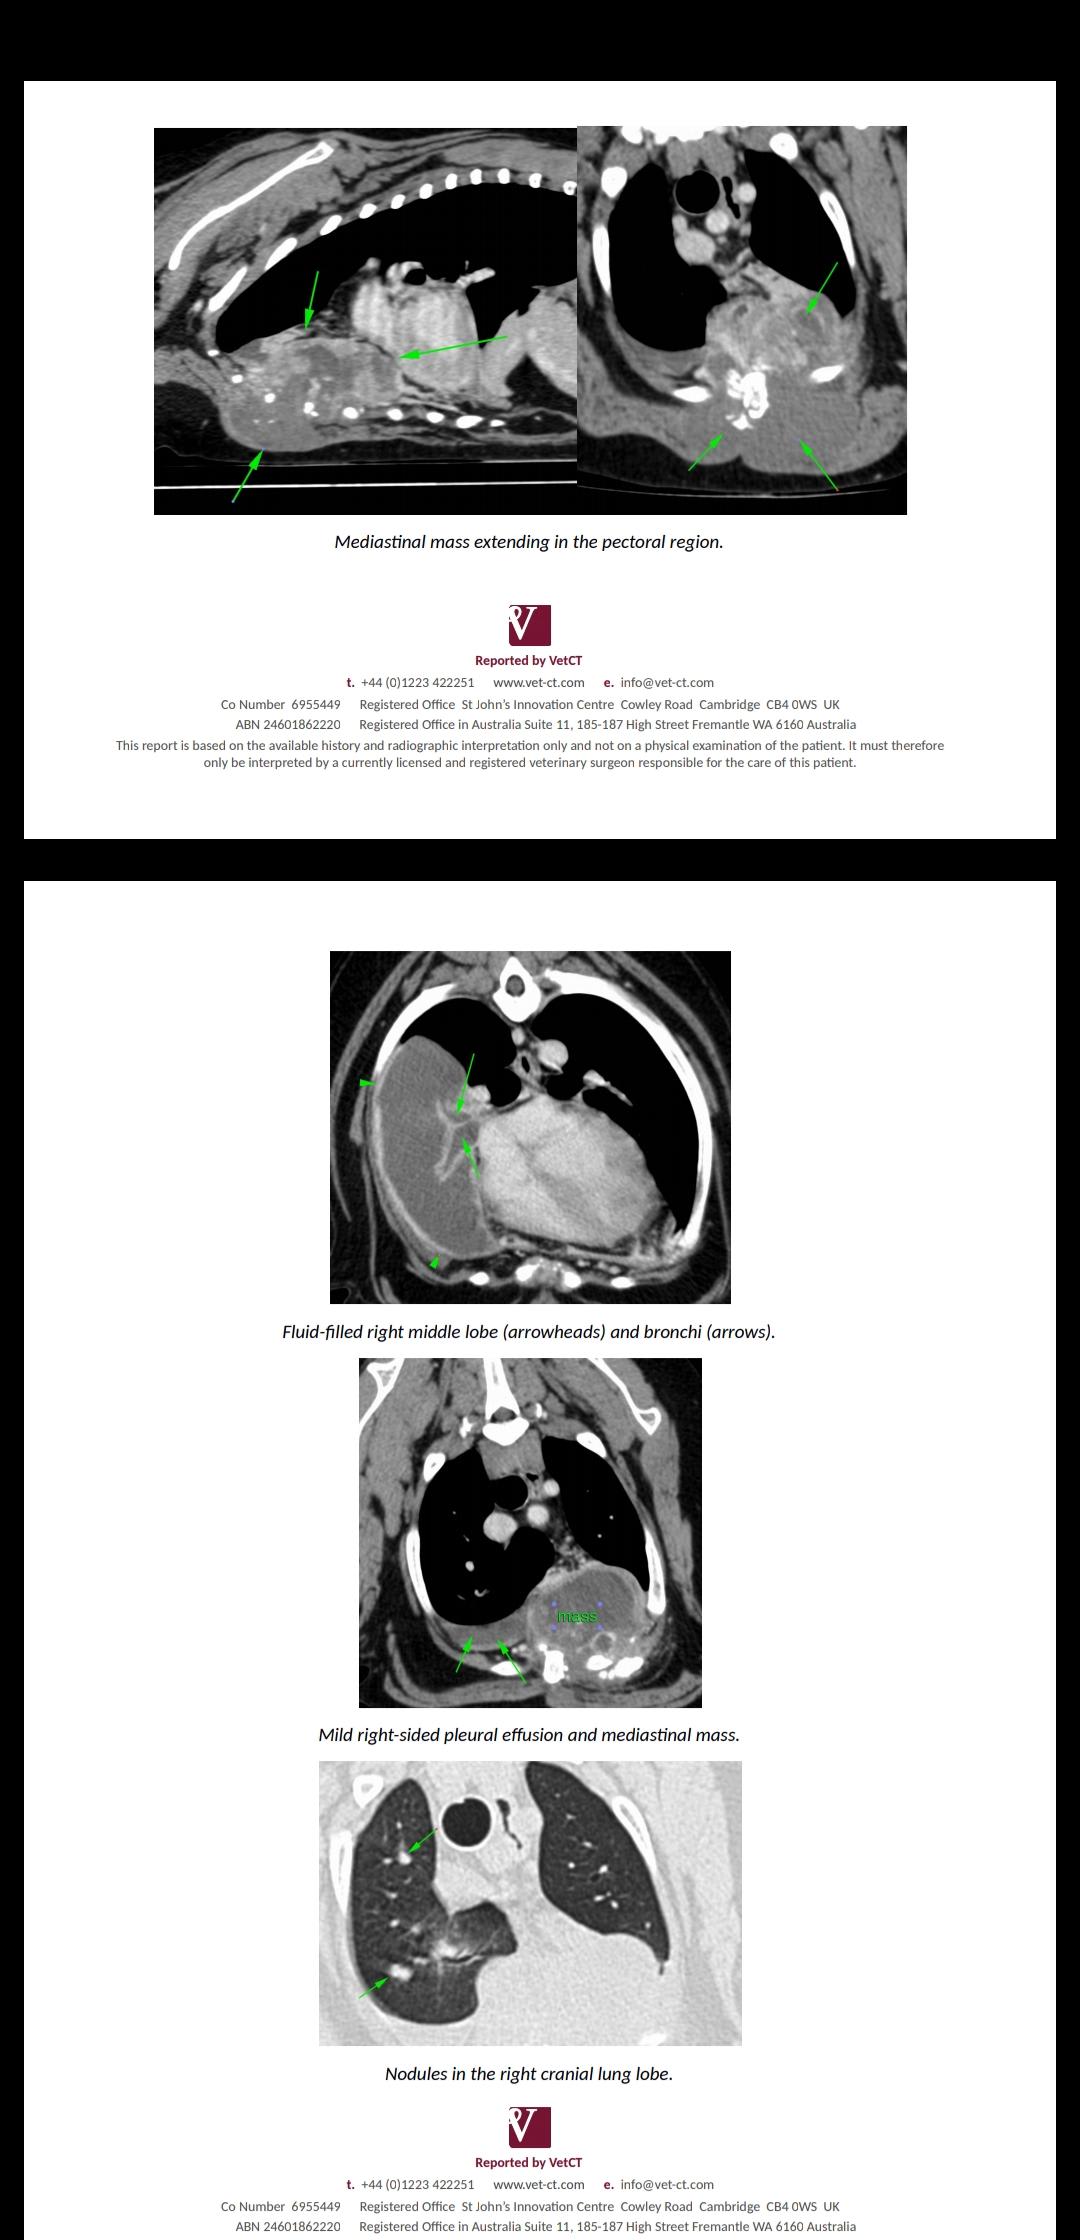

Thanks for using Petco Pet Education Center, formerly Petcoach! The fact that these biopsies have come back inconclusive does not mean that this is not cancer. Unfortunately, this is very likely an aggressive form of cancer. After seeing these images, my main concern is that this is possibly a tumor arising from one of the ribs or sternebrae such as osteosarcoma for instance. In one of the images I see that there is likely pulmonary nodules which are most likely due to metastasis or spread of this cancer. It is hard for me to advice further without being able to look at more images or know more about the case. I would encourage you to check in again with them as another biopsy could be performed. Also, if there is truly already signs of metastasis, the treatment options and prognosis are also limited. I would mention to them the possibility of being referred to a veterinary oncologist who can look at the case with more details and advice further. I really hope they can help you and your boy!